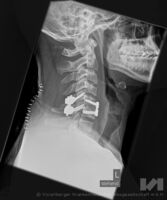

Am Montag, 19.02.2018, begann die Operation um 10 Uhr am Vormittag und dauerte 3,5 Stunden. „Der Patient wies nach seinem fatalen Sturz ein so genanntes Hyperflexionstrauma (Stauchungstrauma) durch die Verletzung des 5. Halswirbels auf. Dieses Trauma war die Ursache für eine gefährliche Instabilität zwischen dem 5. und 6. Halswirbel. Gefährlich deshalb, weil durch ein mögliches Abrutschen der Wirbelkörper 5 und 6 gegeneinander eine schwerwiegende Verletzung des Rückenmarks entstehen kann. Eine operative Stabilisierung der Halswirbelsäule von vorne und von hinten war notwendig (Ventral- und Dorsalstabilisation)“, beschreibt OA Dr. Meusburger. Im Detail heißt dies, dass der Operateur zuerst einen Eingriff von vorne auf die Halswirbelsäule vorgenommen hatte. Die betroffenen Wirbel wurden mit Platte und einem Beckenspan, also einem Knochen aus dem eigenen Becken, der während der Operation entnommen worden ist, stabilisiert.

In der Folge war schließlich noch eine zusätzliche Stabilisierung mit Metallstäben und Schrauben (Implantaten) von der Hinterseite zur vollständigen Konsolidierung notwendig.